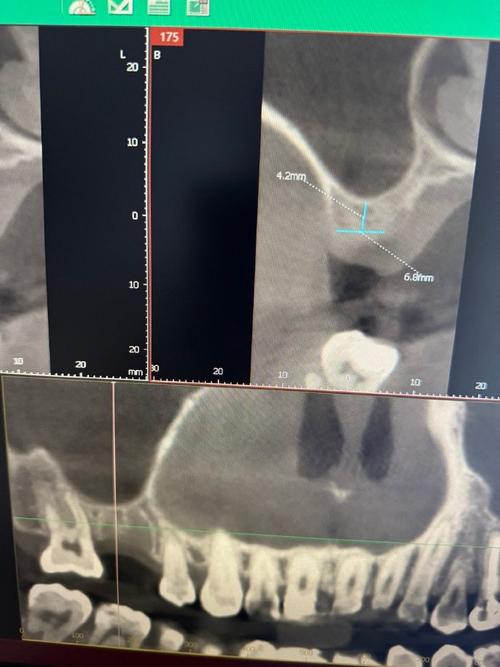

重要解剖结构位置的测量是规避风险的关键,下颌需标记下牙槽神经管的走行及与牙槽嵴顶的距离,安全间距应≥2mm,避免种植体植入时损伤神经导致下唇麻木;上颌需测量上颌窦底壁与牙槽嵴顶的距离,若距离<5mm,需评估是否行上颌窦提升术(分为内提升和外提升),或选择短种植体避开上颌窦;前牙区还需测量鼻底与牙槽嵴顶的距离,确保种植体穿出鼻腔时不会造成鼻腭瘘,邻牙牙根的位置、倾斜角度也需明确,避免种植体侵入邻牙牙根周骨组织,通常种植体与邻牙牙根间距应≥1.5mm。

种植体植入参数的设计需结合骨量和患者咬合力,种植体直径选择上,单颗牙缺失常规选择3.5-4.8mm,后牙区咀嚼力大,可选用5mm以上直径增强稳定性;长度需结合骨高度,一般植入后种植体尖端距离重要解剖结构≥2mm,前牙区美学区可适当缩短种植体长度(8-10mm)以兼顾骨高度和初期稳定性;植入角度需根据邻牙倾斜度、对颌牙位置调整,避免咬合力集中在种植体一侧,通常种植体长轴与牙合面垂直线呈0-15°角,严重骨缺损时可通过角度基台调整修复方向,以下为不同骨密度下种植体选择参考: